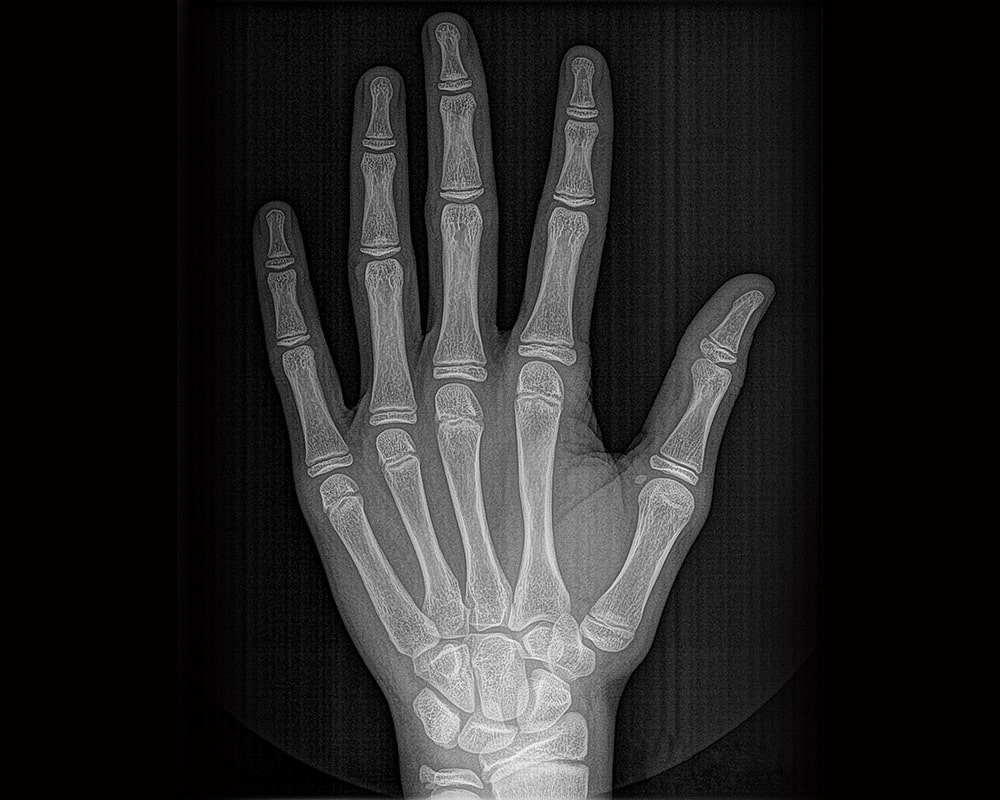

Digital radiographs use electronic sensors to capture images of your teeth, roots, jawbones, and surrounding structures. These images appear instantly on our computers - no film development needed.

We use both intraoral and extraoral digital imaging depending on your needs:

- Intraoral: Bitewing, periapical, occlusal - detailed views inside your mouth